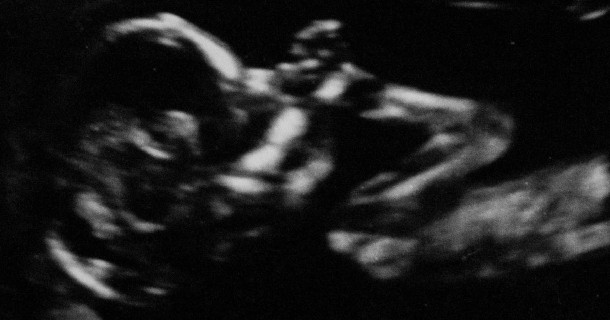

Vilhelm performs a prenatal concert in collaboration with mom and dad

A new human being is on its way to the world. The new person is very close to being ready to enter the world and can already be felt and heard if you listen in the right way.

To celebrate his pending arrival and future ability to see and hear the World without it being filtered by mums belly, Vilhelm is making a little concert.

Vilhelm already has a very active heart that beats around 135 times per minute. Through the use of a fetal doppler ultrasound probe it is possible to hear the heart and other sounds from the womb. These sounds are manipulated to create interesting soundscapes all while being able to hear them as clearly as we can capture them.